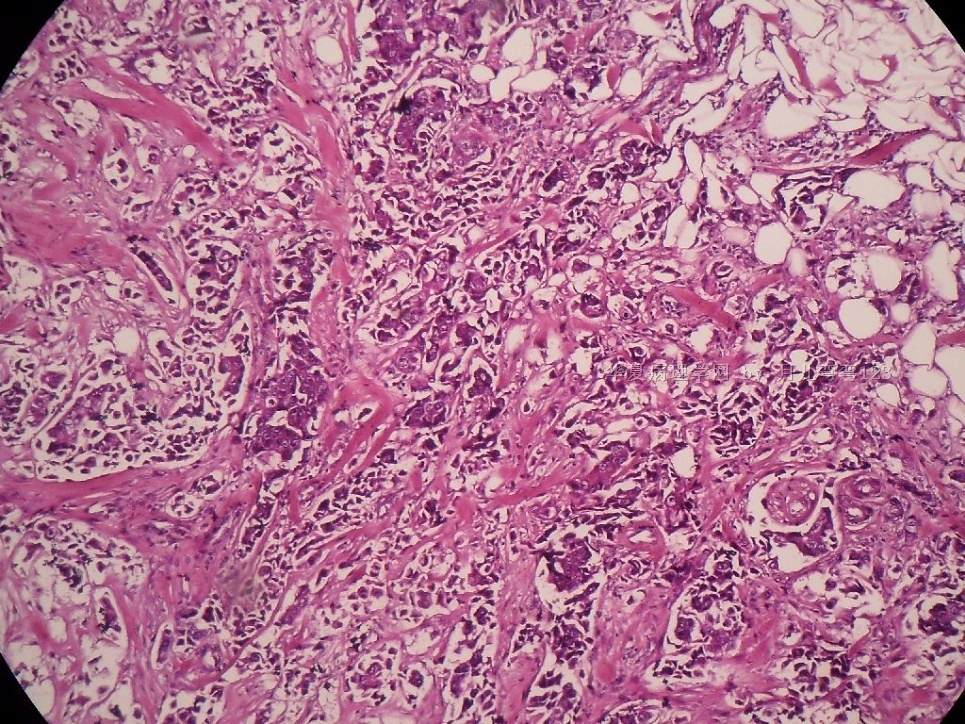

姓    名: ××× 性别:  女 年龄:  45

标本名称:  左侧近乳晕处肿物

简要病史:  患者描述有疼痛

肉眼检查:  肿物一个2.5*2*1厘米,切面灰白质地硬。

• 浸润性导管癌?图1

上皮样细胞,大部分粘附成团成巢,明显浸润。大部分细胞大,核级别高,少数图中见松散的小细胞。未见原位癌。

大细胞考虑浸润性导管癌(3级),小细胞要排除小叶癌。如果有条件请做免疫组化。

Most likely it is INVASIVE DUCTAL CARCINOMA.

DO ER/PR/HER2 STAINS

应该是浸润性导管癌,标本可能有部分自溶现象。